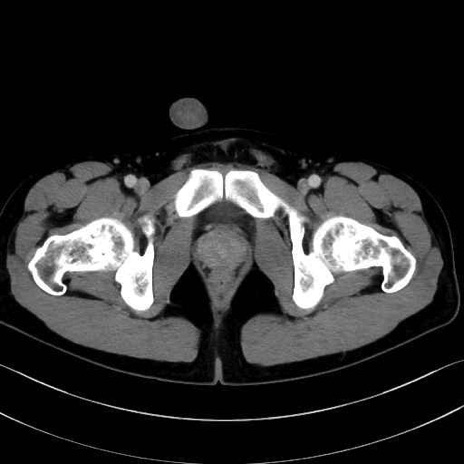

長内転筋(Adductor longus muscle)のCT画像の解剖

恥骨筋 (Pectineus)

長内転筋 (Adductor longus)

短内転筋 (Adductor brevis)